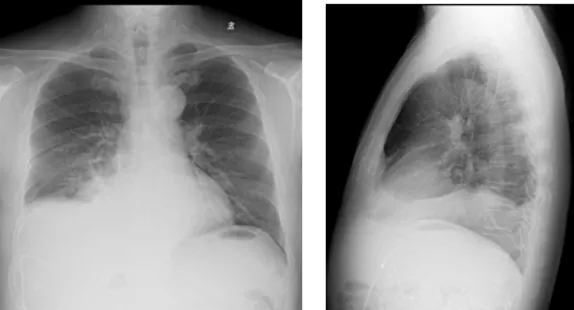

影像學(xué)檢查結(jié)果

右肺炎癥不能排除,請結(jié)合臨床。右側(cè)少量胸腔積液

右側(cè)胸腔積液細(xì)胞學(xué)檢查結(jié)果

(右側(cè)胸腔積液)細(xì)胞學(xué)檢查見少數(shù)惡性細(xì)胞,形態(tài)考慮腺癌細(xì)胞。